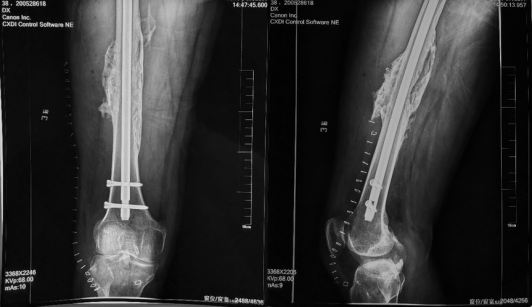

图1、2  右大腿正侧位 可见股骨内固定物在位,断端周围高密度异位骨化包绕,断端骨皮质不连续。